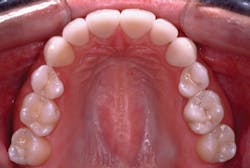

When all of these technologies are added into a posterior composite protocol, it allows the dental team to place excellent restorations in 30% to 60% less time (Figs. 3 and 4).